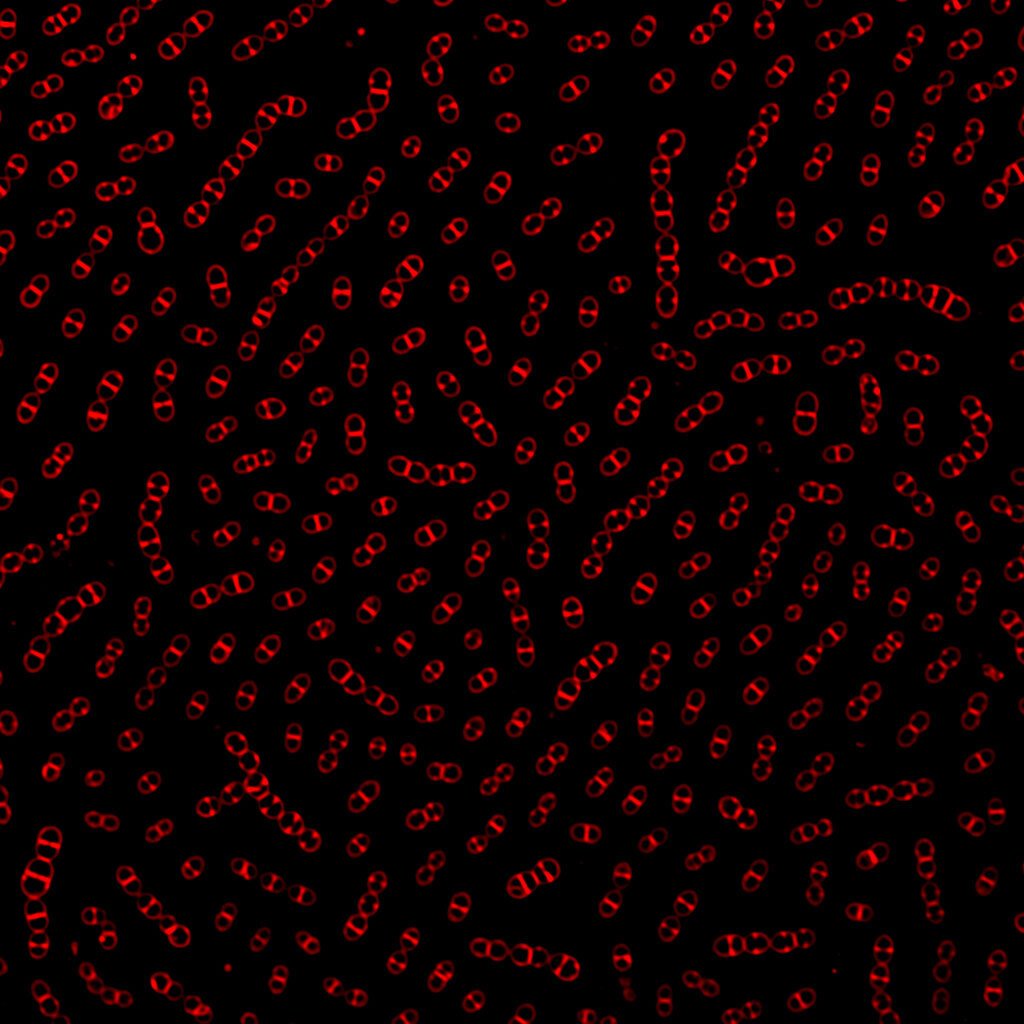

A major focus is on infections caused by the bacterium Streptococcus pneumoniae (the pneumococcus). Pneumococci are the major cause of milder respiratory tract infections such as otitis and sinusitis, but also a major cause of more severe infections such as community-acquired pneumonia, with or without septicemia, and meningitis. Despite being disease-causing pathogens, these bacteria are also commonly found colonizing healthy individuals.

We aim at understanding mechanisms for how and why these common bacteria cause diseases with even lethal outcome, and how they are spread in the society. Together with the Public Health Agency, we are following the effects of introducing pneumococcal conjugated vaccines (PCVs) in the childhood vaccination program.